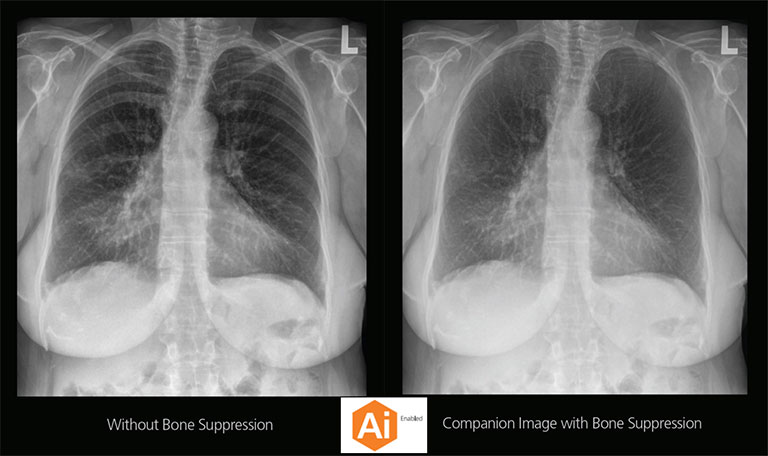

Our Carestream Focus HD 35/43 Retrofit Detectors, powered by Image Suite Software, are an ideal solution to step up to full digital X-ray for customers who simply cannot compromise on image quality. It seamlessly integrates into existing setups, bringing the power of full digital X-ray with minimal disruption and maximum clarity, along with the following benefits: